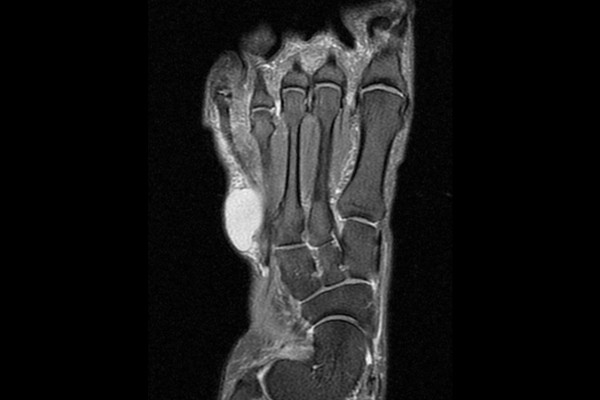

자세한 확인을 위해 MRI 촬영을 진행하였고, MRI에서 하얗게 보이는 물혹이 확인되었습니다.

측면에서 확인했을 때 역시 확연히 보이는 물혹이 확인되어 우측 발 결절종(Ganglion foot dorsum)을 진단하였습니다.